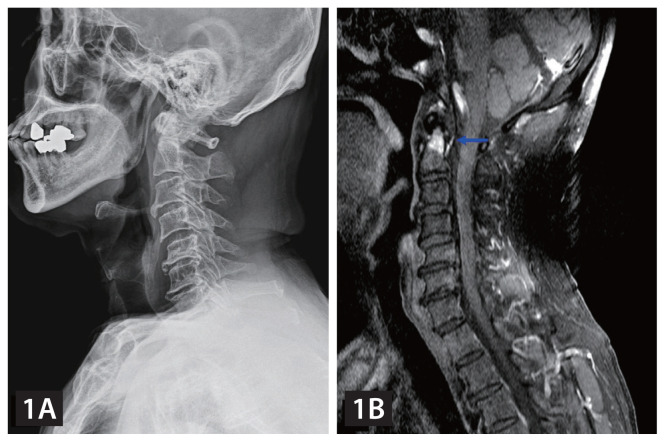

寰枢关节急性痛风性关节炎。

Acute gouty arthritis of the atlantoaxial joint.